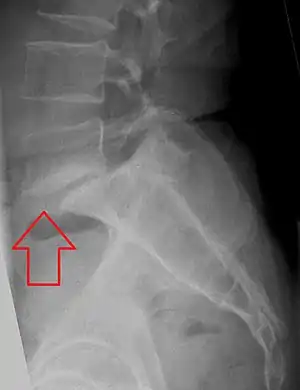

| X-ray of the lateral lumbar spine with a grade III anterolisthesis at the L5-S1 level. | |

Spondylolisthesis is the displacement of one spinal vertebra compared to another. While some medical dictionaries define spondylolisthesis specifically as the forward or anterior displacement of a vertebra over the vertebra inferior to it (or the sacrum),[1][2] it is often defined in medical textbooks as displacement in any direction.[3][4] Spondylolisthesis is graded based upon the degree of slippage of one vertebral body relative to the subsequent adjacent vertebral body.[5] Spondylolisthesis is classified as one of the six major etiologies: degenerative, traumatic, dysplastic, isthmic, pathologic, or post-surgical.[6] Spondylolisthesis most commonly occurs in the lumbar spine, primarily at the L5-S1 level with the L5 vertebral body anteriorly translating over the S1 vertebral body.[6]

Classification by degree of the slippage, as measured as percentage of the width of the vertebral body:[14] Grade I spondylolisthesis accounts for approximately 75% of all cases.[6]

- Grade III: 50–75%